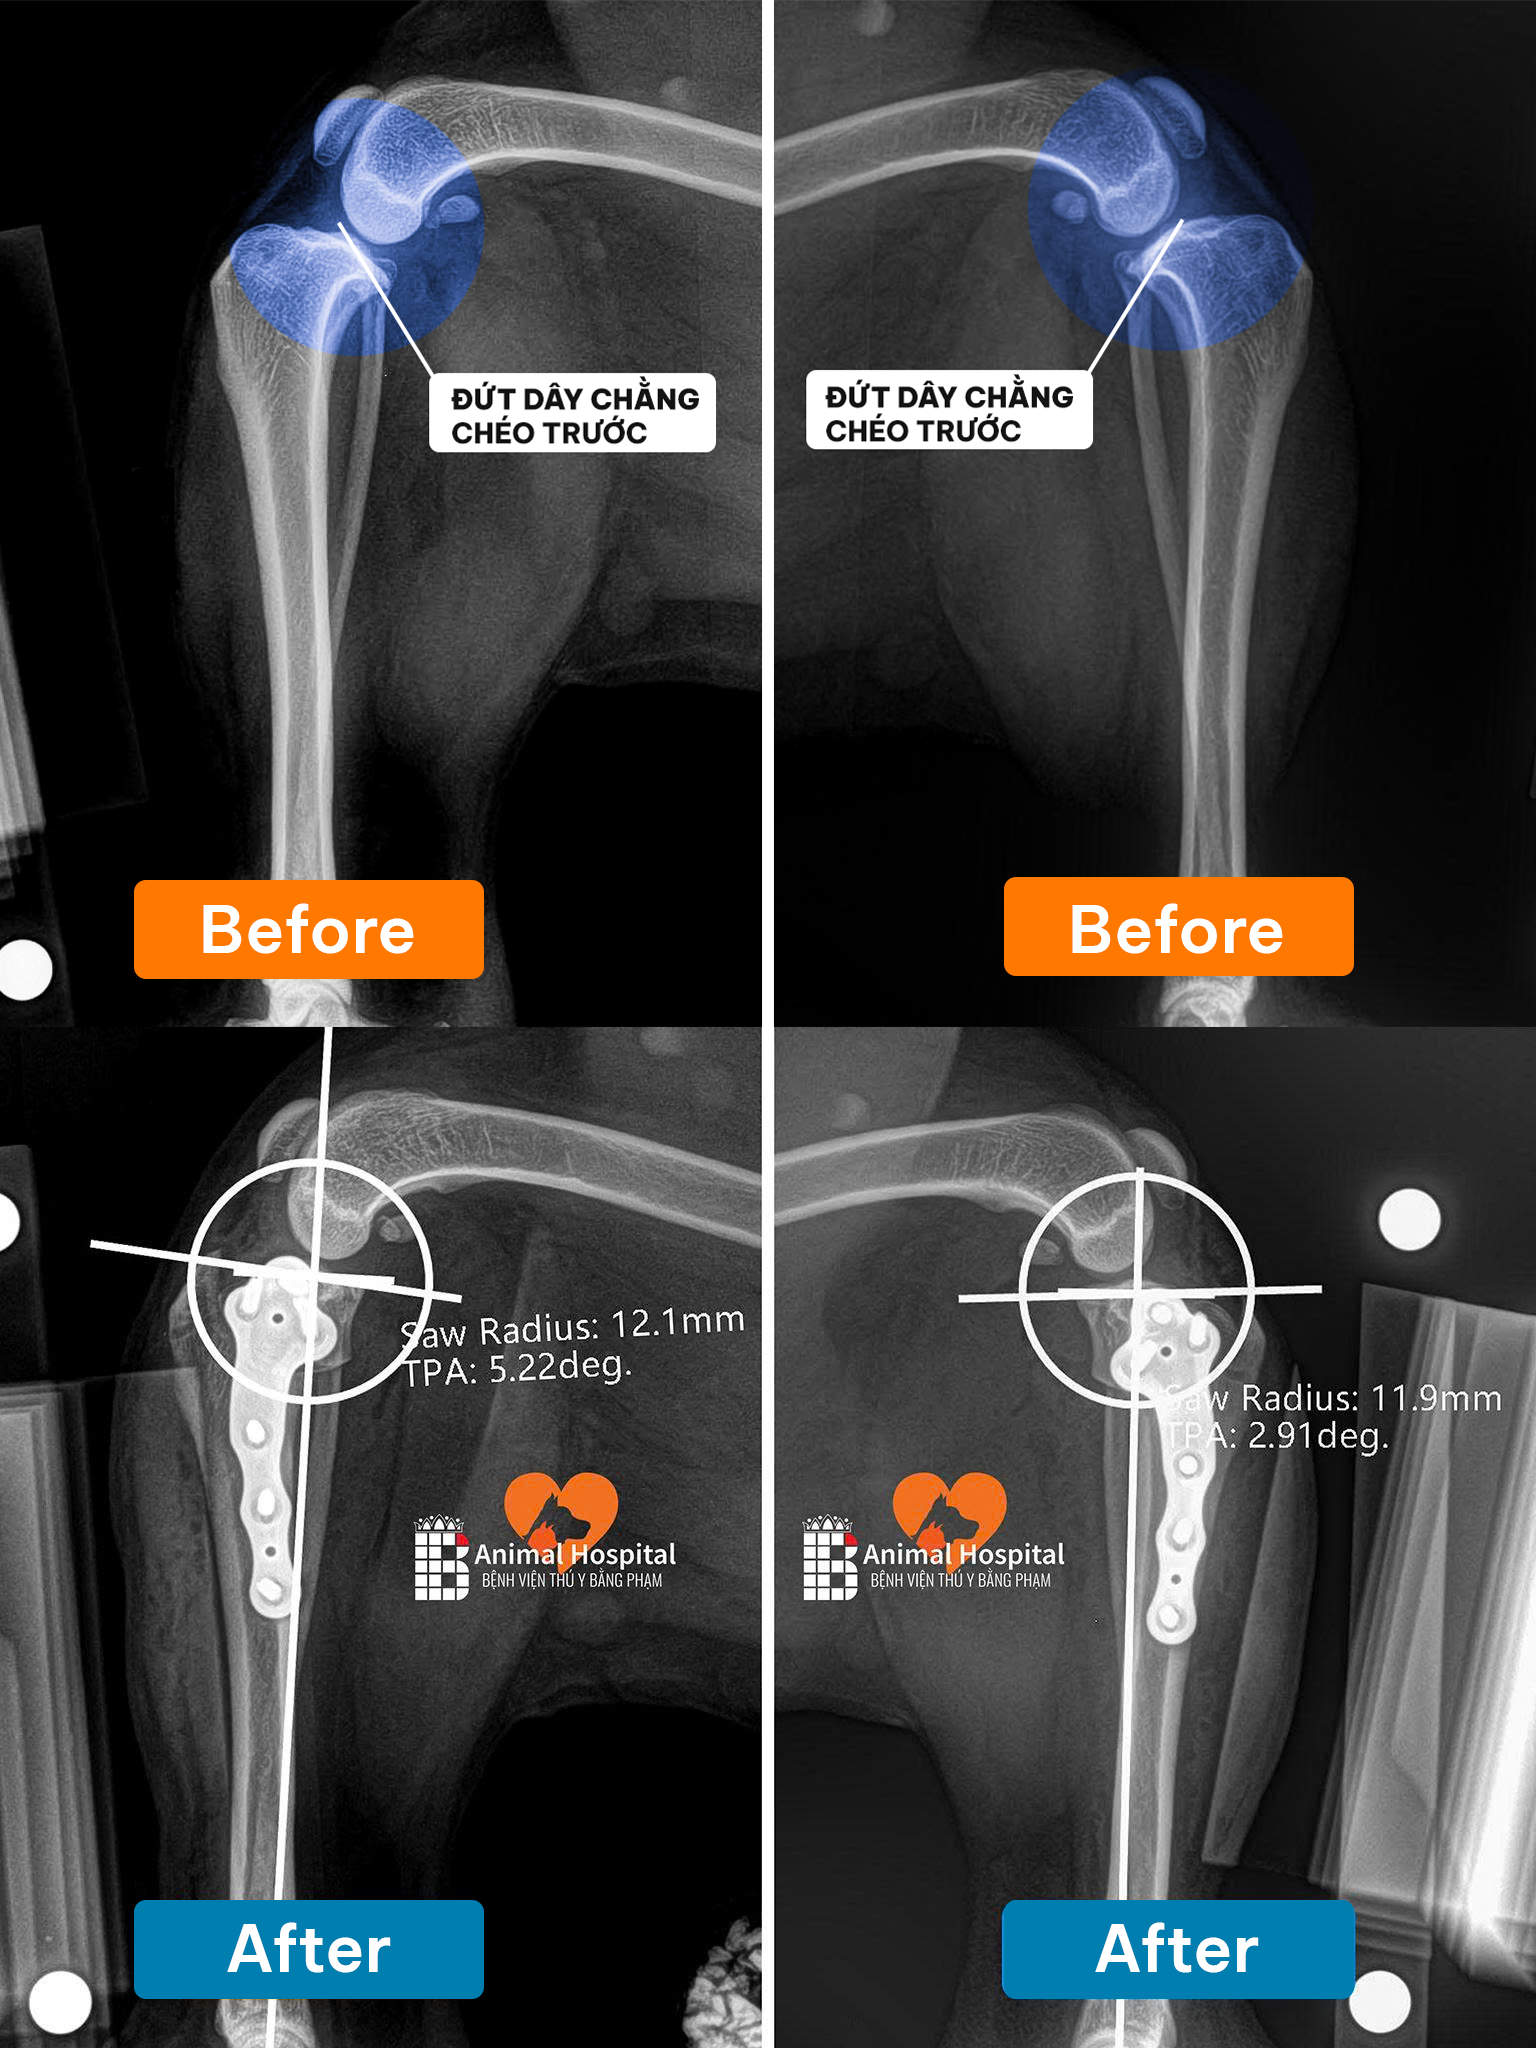

Qua thăm khám khẩn cấp, các bác sĩ xác định bé bị gãy đầu gần xương chày chân phải sau, kèm tổn thương mô mềm nghiêm trọng. Với các trường hợp chó bị cắn gãy chân, chấn thương vật lý thường đi kèm với những tổn thương bên trong. Điều đáng lo ngại hơn là chức năng gan và thận của bé đã bị ảnh hưởng rõ rệt do sốc chấn thương.

Để đảm bảo hiệu quả phục hồi vận động cao nhất cho tình trạng chó bị cắn gãy chân, các bác sĩ bóc tách mô mềm tiếp cận ổ gãy, nắn chỉnh các mảnh xương về đúng trục giải phẫu, sau đó áp dụng hệ thống nẹp vít PRCL, một giải pháp cố định xương tiên tiến giúp giảm thiểu diện tích tiếp xúc giữa nẹp và xương, từ đó bảo vệ nguồn cung cấp máu cục bộ và tạo điều kiện tối ưu cho quá trình liền xương.